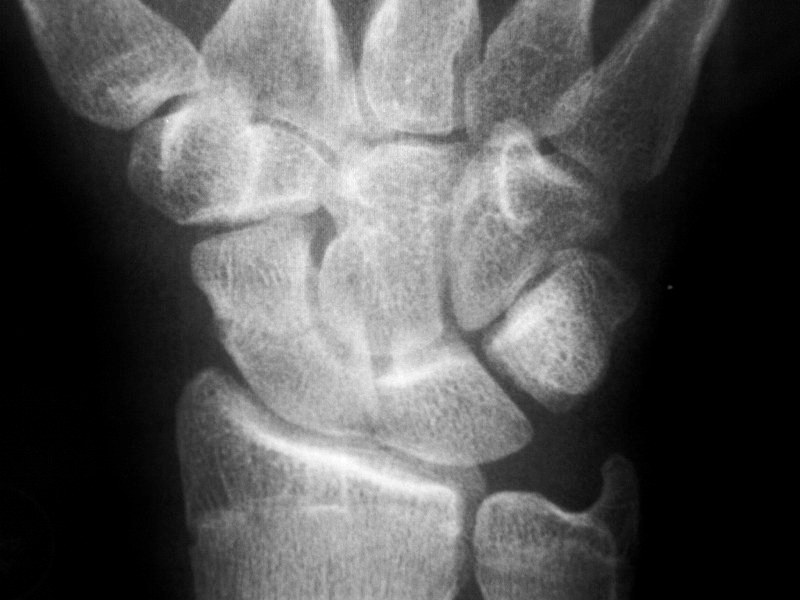

У Доктора Марио представлены рентгенограммы поперечного перелома ладьевидной кости с удовлетворительным стоянием отломков. У Валентина Львовича похожая патология, только со смещением костных отломком.